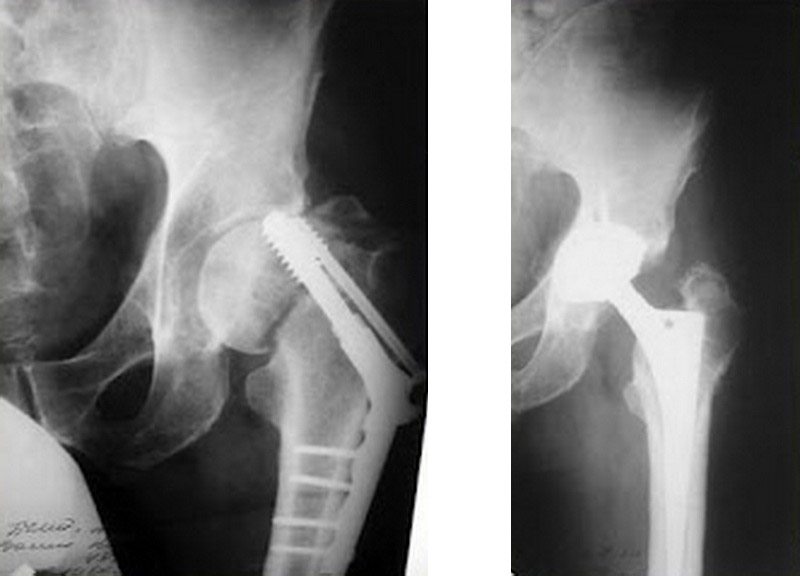

| Неправильне зрощення | Корекційний остеосинтез або фізіотерапія |